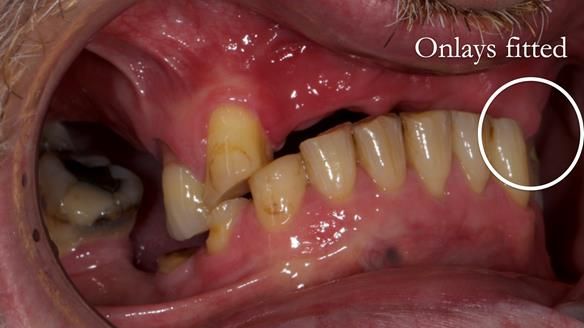

2. Onlay preparations: Composite onlays were fitted for his upper left premolars to repair these teeth and support the new denture.